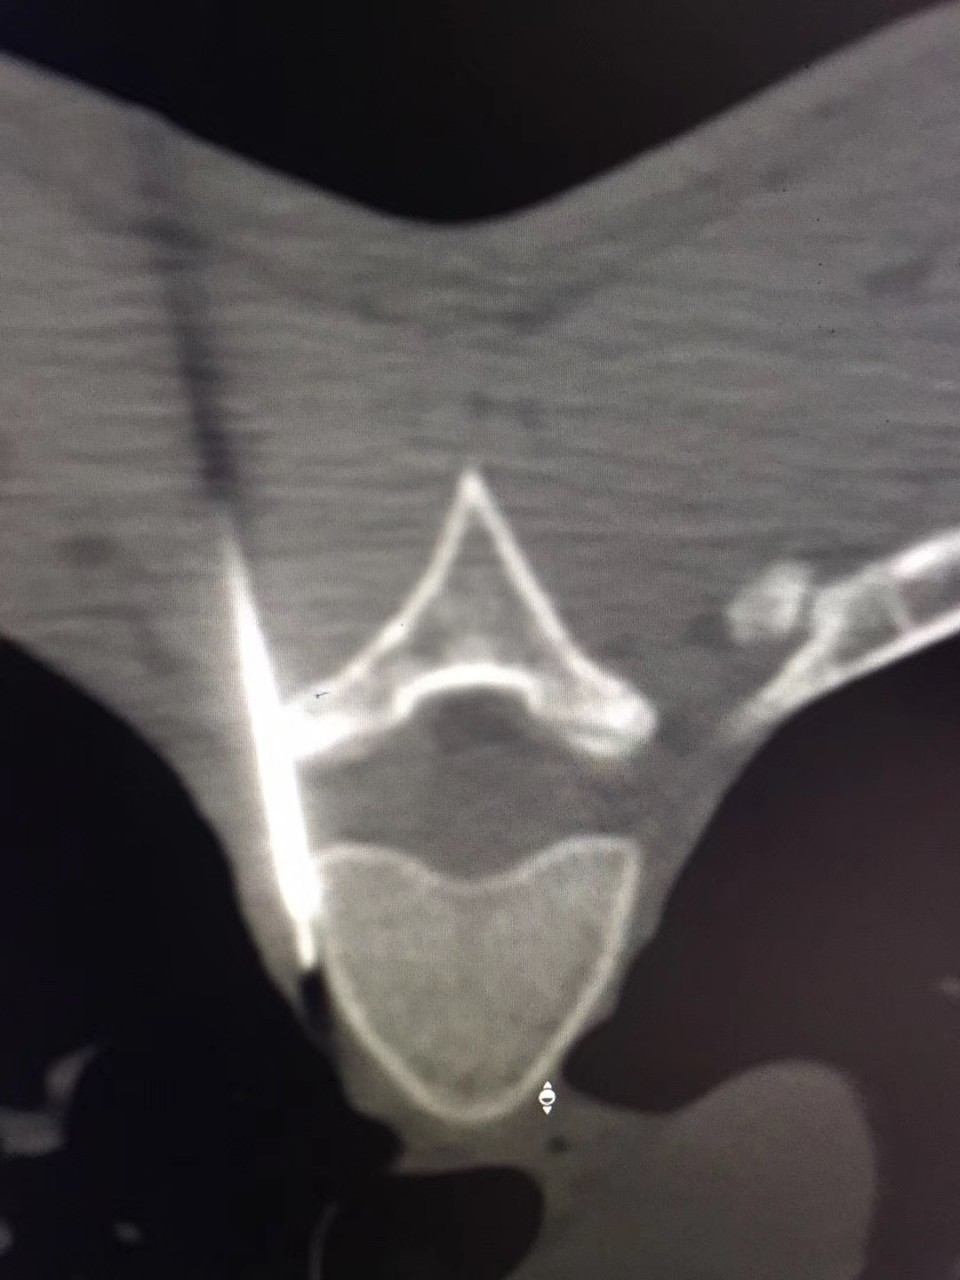

近日,疼痛科接诊了一位18岁的多汗症患者,该患者反复双足发汗多年,伴手上皮肤脱落。曾就诊于省内外多家医院,但均未获得满意的疗效。听闻安徽医科大学第一附属医院疼痛科是一种以微创介入方法治疗各种疑难病痛的科室,遂前往就诊。疼痛科副主任医师宋阳在对该患者病情特点进行综合的分析后决定对其进行CT引导下胸交感神经链无水酒精化学毁损术。当日手术结束后该患者立马感觉到双手不再是以前那样冰冷,逐渐回复了正常的温度,且发汗症状完全消失。在观察了数日之后无任何的复发症状,负责该患者的副主任医师宋阳称,通过无水酒精的化学毁损作用中断汗腺神经分泌的神经传递过程,可永久的减少出汗,达到临床治愈水平。

对于诊断明确的原发局部性多汗症患者,传统的治疗手段有局部及全身药物治疗以及激光、微波等物理疗法。目前比较主流的有CT引导下经皮穿刺胸交感神经化学阻滞及外科手术治疗。其中CT引导下交感神经链阻滞技术成功率甚至可达100%,治疗效果与胸腔镜下交感神经链切断术效果相当,应用无水酒精能达到对交感神经链的功能有效长久的阻滞,达到良好的治疗效果,且创伤更小、并发症更少。胸腔镜下交感神经切断术是治疗手、头面部及腋窝多汗症的一种二线治疗方案。但其术后疼痛、气胸、神经病变累及上肢、霍纳综合症以及代偿性多汗症发生率较高。